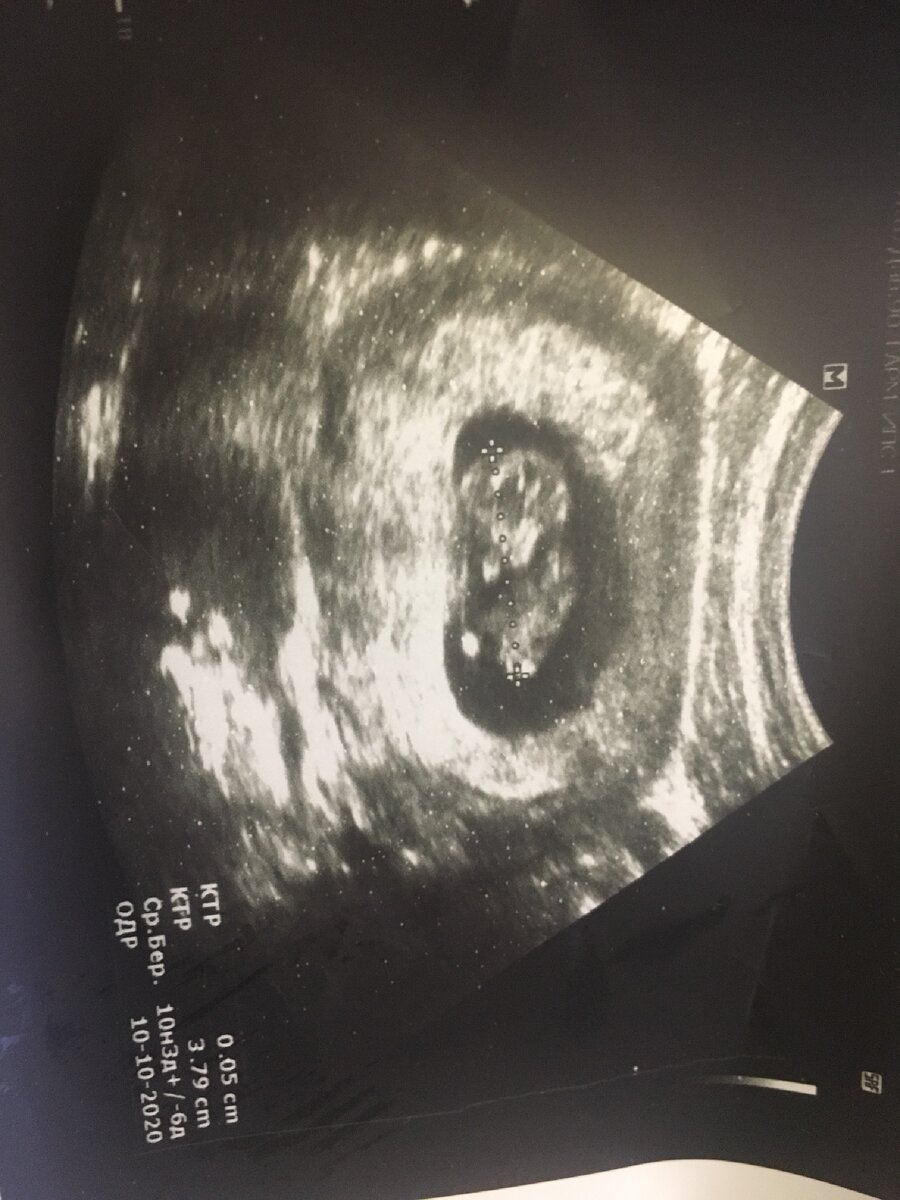

В назначенный день, мы всей палатой отправились на УЗИ. Первая зашла девушка со сроком 12 недель, вышла серьезной, сказала что все нормально. То же самое было со второй. Третьей зашла самая весёлая из нас. В кабинете была очень долго. Вышла рыдая и побежала прочь. У меня был ступор: бежать успокаивать или идти в кабинет. Решила пойти на УЗИ, так как была моя очередь. Коленки подкашивались, если честно. Врач долго водила датчиком, всматриваясь в экран. Я не могла проронить ни слова, дышала через раз. Врач после молчания сказала что ничего не видит, совсем ничего ни в матке ни в трубах. Спросила точно ли я делала тест, про сроки спросила. Сказала что нужно подождать неделю и тогда все будет понятно.

Узи через неделю все повторилось - врач ничего не увидела. Отправила на вакуум, как сказала, на всякий случай. Беременность не понятно есть или нет, а если есть, что подтверждает ХГЧ, то замерла она почти сразу. Я была опустошена и раздавлена. Все мечты рассыпались как карточный домик. Четко решила для себя- раз жизнь не даёт мне детей, значит так тому и быть